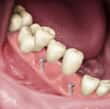

| Implantater er ofte veldig stabile samt at de lett passer inn i munnen. | Implantater fungerer som erstatning for enkelte tenner. |